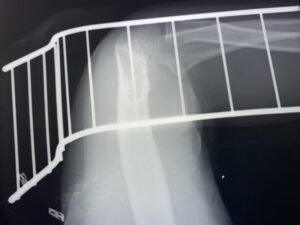

さわやか千葉県民プラザ(上腕骨外科頸骨折)

さわやか千葉県民プラザ(上腕骨外科系骨折)